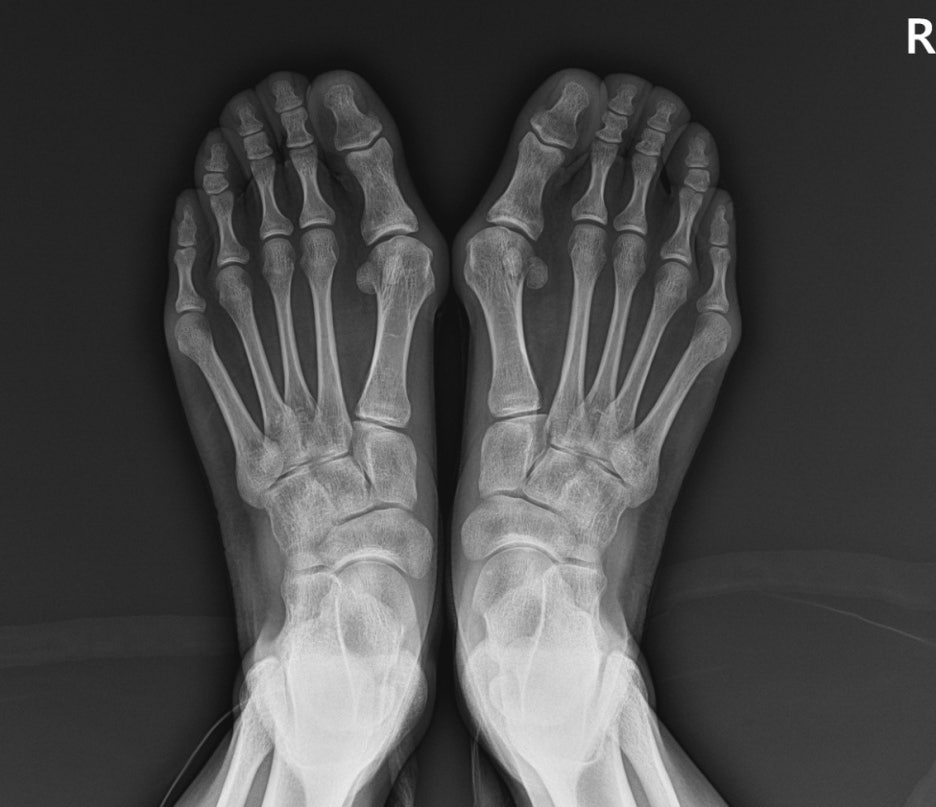

- 영상 검사(X-ray): 관절 간격이 좁아졌는지, 뼈에 미세한 골미란(깎임)이 있는지 확인합니다.

진단: X-ray상 관절 간격이 매우 좁아졌고 엄지발가락이 옆으로 회전 변형된 상태 확인.